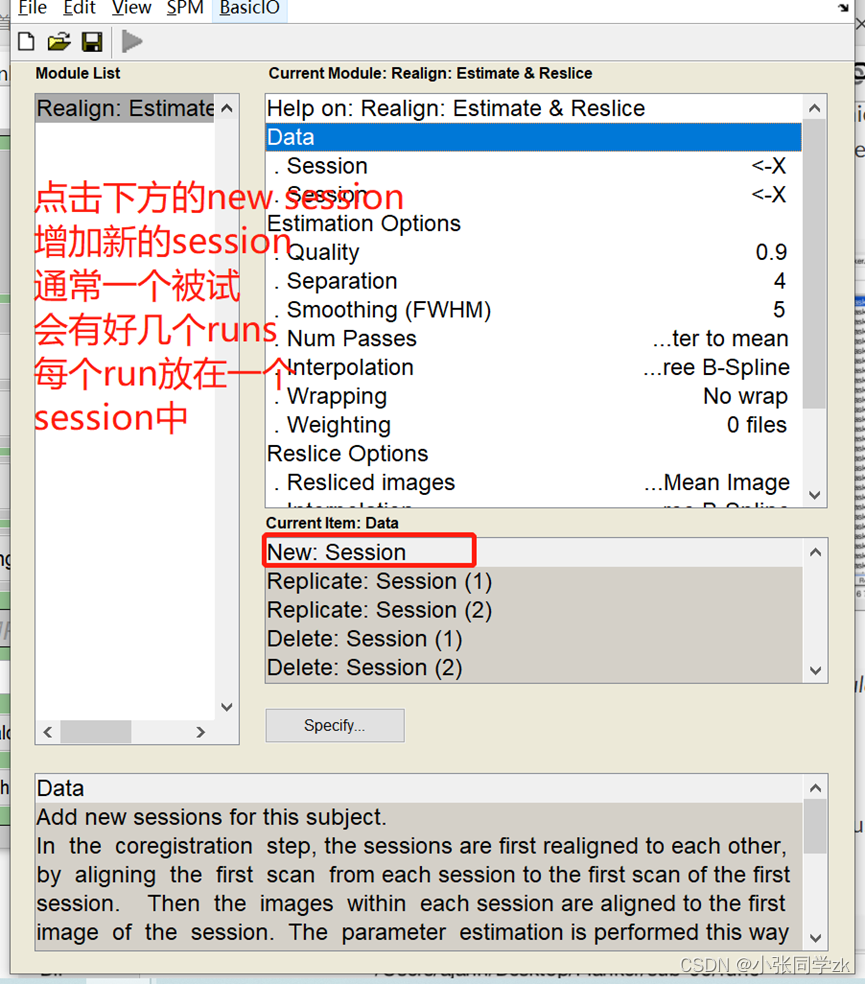

3.1 Realignment

添加数据:双击session按钮,找到需要添加数据的文件夹路径,选择sub-08_task-flanker_run-1_bold.nii,1 “1”是第一个frame或者volume,我们需要在Filters下面输入1:146(如果不知道多少个volumes,就输入1:1000,这样就会把所有的volumes加载进去),然后点击enter,右键select all,点击done,就得到一个run的所有数据。如下图所示。

为了精确找到文件,在 .* 的左边输入run-1。